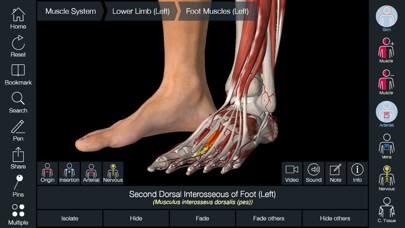

Downloading Essential Anatomy 5 IPA for iOS is a convenient and useful way to explore the world of human anatomy right from the comfort of your iPhone or iPad. This app provides a comprehensive and detailed view of the human body, allowing users to interact with various systems and structures. With stunning 3D graphics, it offers a visually captivating experience that aids in understanding and learning about the complexities of the human body. Whether you are a medical student, healthcare professional, or someone with a general interest in anatomy, Essential Anatomy 5 IPA is a must-have app that provides a wealth of knowledge at your fingertips. The app’s intuitive interface and easy navigation make it accessible to users of all levels of expertise. With just a few taps, you can delve into different layers of the body, explore various organs, muscles, and bones, and gain a deeper understanding of human anatomy. Download Essential Anatomy 5 IPA today and elevate your knowledge and appreciation of the human body.

The Essential Anatomy 5 IPA for iPhone is an incredible tool for medical students, professionals, and anyone interested in learning more about the human body. This app provides a comprehensive and detailed 3D model of the human anatomy, allowing users to explore and study different parts of the body with ease. With its user-friendly interface and interactive features, users can zoom in, rotate, and examine every angle of the human body, from bones and muscles to organs and systems. The app also provides in-depth information about each structure, making it a valuable resource for studying and understanding the intricacies of human anatomy. Whether you’re a medical student preparing for exams or simply curious about the wonders of the human body, the Essential Anatomy 5 IPA for iPhone is an essential tool to have at your fingertips.

Essential Anatomy 5 IPA MOD IOS is a revolutionary app that has changed the way we learn about the human body. With its advanced features and stunning visuals, this app provides an immersive and interactive experience for users. Whether you are a medical student, healthcare professional, or simply interested in learning about anatomy, Essential Anatomy 5 is a must-have tool. It offers a comprehensive library of detailed 3D models, allowing users to explore every aspect of the human body. From the skeletal system to the muscular system, nervous system to cardiovascular system, this app covers it all. Additionally, it provides in-depth information on each structure, including names, functions, and clinical relevance. With its user-friendly interface and intuitive controls, navigating through the app is a breeze. Overall, Essential Anatomy 5 IPA MOD IOS is an essential resource that brings anatomy to life, making it an invaluable tool for anyone interested in the human body.

This app provides a comprehensive and detailed 3D representation of the human body. With over 8,200 anatomical structures, including muscles, bones, organs, and more, it offers a level of accuracy and depth that is unparalleled. Whether you are studying for an exam or explaining a medical condition to a patient, Essential Anatomy 5 IPA has the information you need.

Essential Anatomy 5 IPA allows users to interact with the 3D models, zooming in and rotating them to explore every angle. The user-friendly interface makes navigating through the app a breeze, and the intuitive controls ensure that anyone, regardless of their level of expertise, can easily explore and understand the complex anatomical structures.